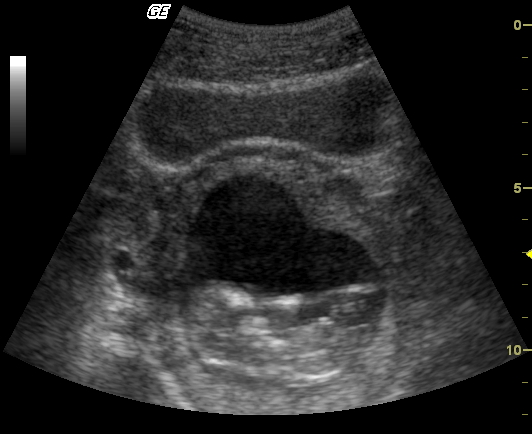

Mam war nun bei ihrem Frauenarzt und der machte per Ultraschall das erste Foto von mir:

Ich stellte fest, dass ich viel zu klein bin und schnell wachsen muss, um besser auf den nächsten Bildern erkannt zu werden.

Die Ärztin wog noch Mama und mich und maß den Bauchumfang, demnach wiegen wir zusammen 64,5 kg und Mamas Bauchumfang beträgt 80,5 cm.